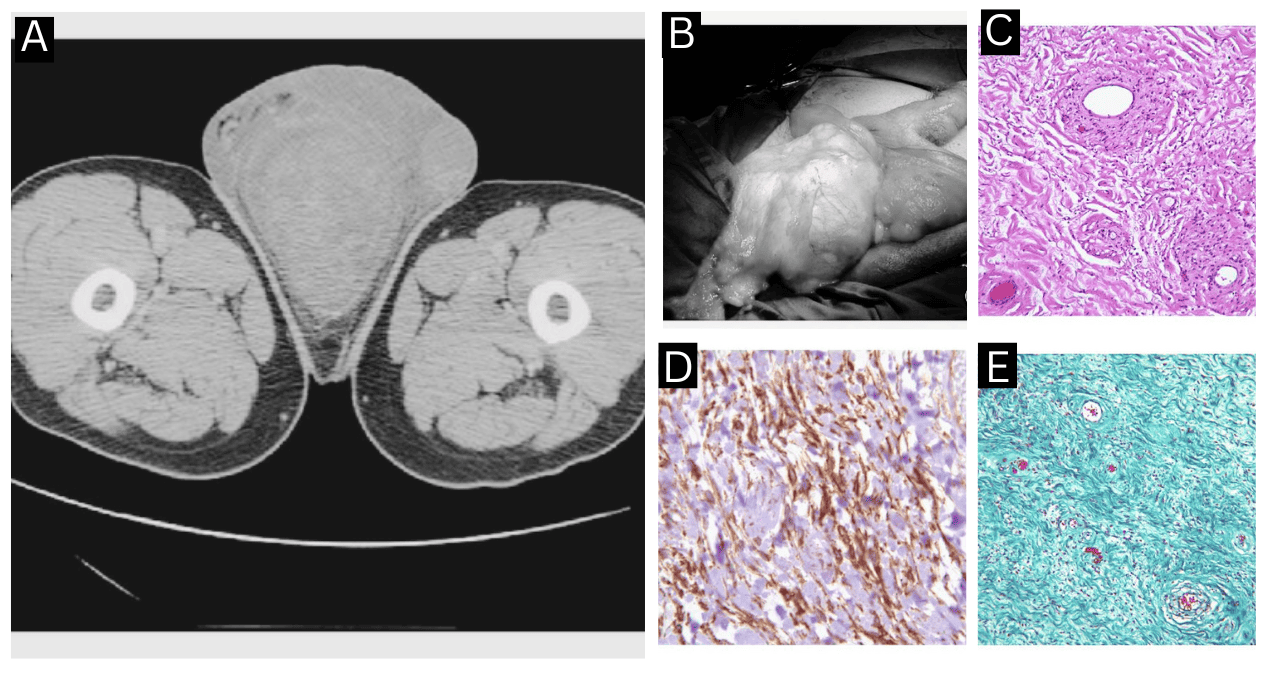

El estudio histopatológico reveló un tumor paucicelular con áreas fibrosas y mixoides, compuesto por escasas células fusiformes sin atipia ni actividad mitótica.

Sumado a eso, se observaron abundantes vasos de paredes engrosadas inmersos en un estroma edematoso con presencia de fibras de colágeno. En la periferia, se identificaron restos de músculo esquelético.

En el análisis inmunohistoquímico, las células tumorales mostraron positividad para CD34, desmina y alfa-SMA, mientras que resultaron negativas para la proteína S-100. Estos hallazgos fueron compatibles con el diagnóstico de angiomixoma agresivo del escroto.

Así mismo, se caracteriza por un estroma laxo y mixoide con abundantes vasos de paredes engrosadas y células fusiformes sin atipia. La inmunohistoquímica suele demostrar positividad para marcadores mesenquimales como vimentina, desmina, actina y CD34, y negatividad para proteína S-100, lo que ayuda a diferenciarlo de otras neoplasias mixoides como el angiomiofibroblastoma, el mixoma y el liposarcoma mixoide.